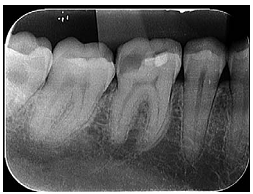

A radiografia apresentada refere-se ao exame de um paciente de vinte e cinco anos de idade que se queixava de dor espontânea na região inferior direita da face. Na realização do teste térmico de sensibilidade pulpar a frio no dente 46, houve exacerbação da dor.

Nesse caso clínico, o diagnóstico do paciente é de pulpite